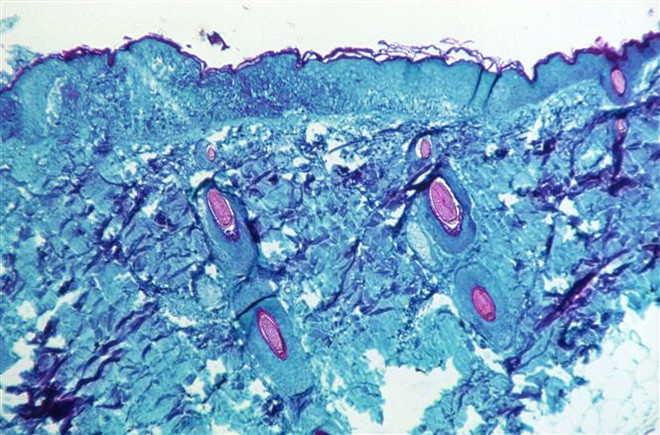

Mexico ghi nhận ca bệnh đậu mùa khỉ đầu tiên, có thể từ Hà Lan ảnh 1Một phần tế bào da của một con khỉ bị mắc bệnh đậu mùa khỉ. Ảnh: REUTER/TTXVN